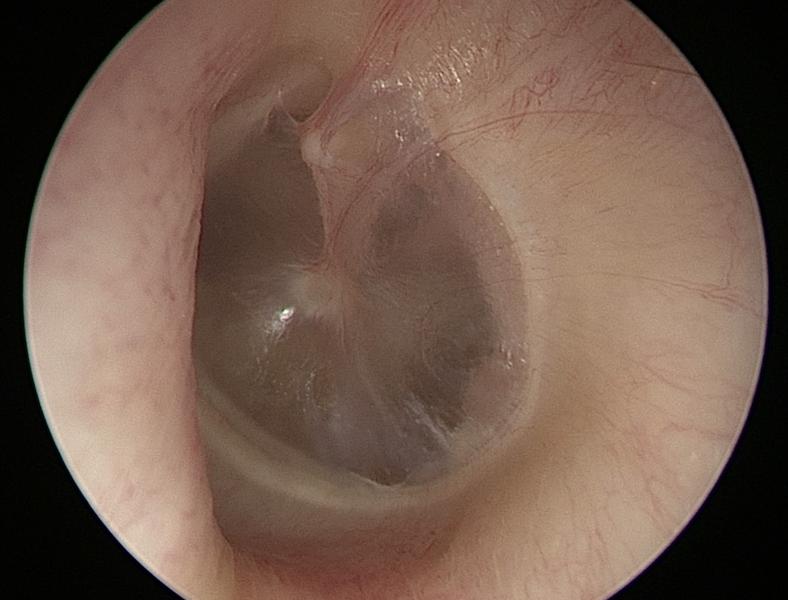

Normal Tympanic Membrane